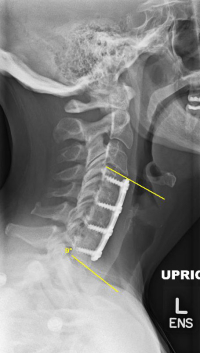

(Click to Enlarge Image) Early kyphosis development. The yellow lines are on the edges of the two vertebra. These lines should diverge (spread apart in front) but instead converge due to the kyphosis.

(Click to Enlarge Image) Neutral X-ray of degenerative kyphosis. The yellow lines note a 22 degree kyphosis. Patient has failed all non-operative care and is miserable.